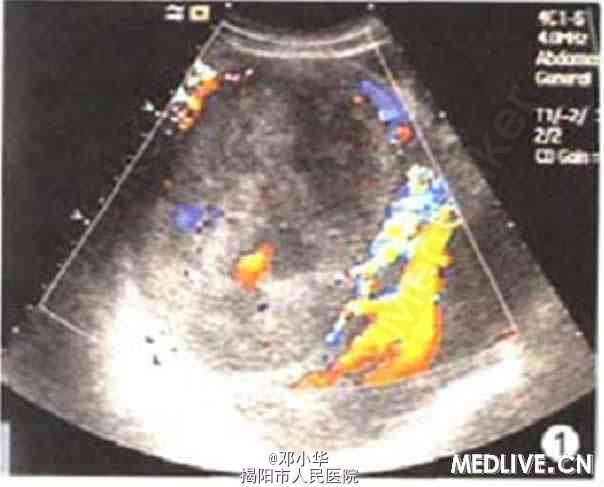

体格检查:体温正常,无消瘦、乏力,皮肤巩膜无黄染,上腹未及肿块,肝肋下3指,脾未扪及。 实验室检查:肿瘤指标正常;乙肝病毒表面抗原(HBsAg)、乙肝病毒e抗体(HBeAb)、乙肝病毒核心抗体(HBcAb)均阳性;。碱性磷酸酶(ALP)521.5 U/L。谷氨酰转肽酶(GGT)180 U/L,丙氨酸氨基转移酶(ALT)85 U/L。 超声检查示右肝内见12.7cm×12.2 cm的实质性肿块(图1)。边界清,无声晕,内部回声强弱不均。低机械指数成像技术下SonoVue超声造影显示动脉期10 s时肿块大部分迅速增强,高于同期肝实质,25 s后大部分消退(图2)。低于同期肝实质,提示恶性病变(肝癌)。 腹部CT示肝增大,右叶一巨大肿块(图3),大小约9.8 cm×13.2 cm。CT提示肝恶性肿瘤,首先考虑肝细胞性肝癌伴淋巴结转移,伴肺部转移,矽肺待排。